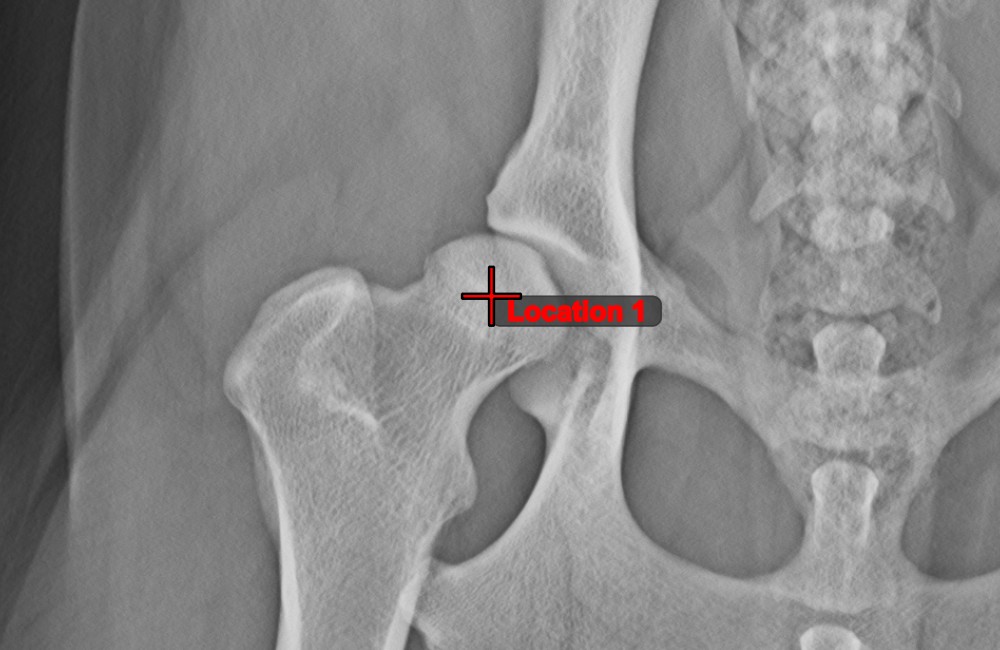

Measurement Point

Mark simple points on the image using the Measurement Point tool. Each point is assigned with a letter for better identification.

Modify the position of the points on the image by using the Select/Move Item tool. Select the point by using the assigned mouse button of the tool, and then move it freely anywhere on the image.